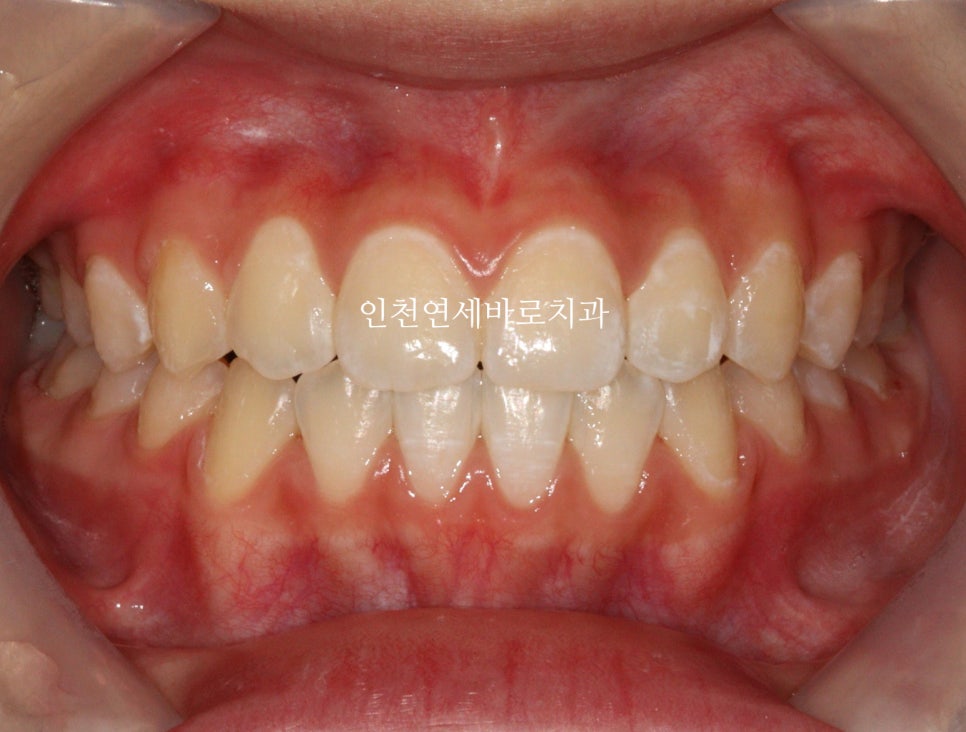

2024년 11월 11일 – 치료 완료

치아배열도 좋습니다.

아이가 치료가 끝난 후 안아프고 좋았다. 친구들이 부러워했다. 라는 말을 해서 뿌듯했습니다.